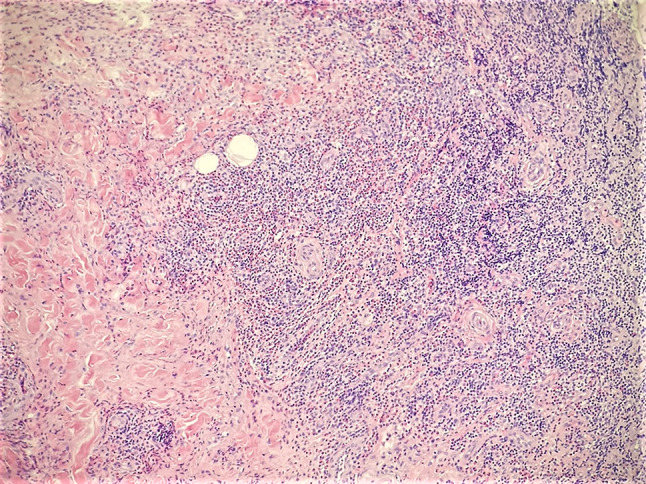

A fine-needle aspirate was taken of the mass and cervical lymph nodes, which demonstrated atypical T-cells and prominent eosinophilia. A subsequent incisional biopsy revealed extensive lymphoid and eosinophilic infiltrate, follicular hyperplasia with germinal centers, extensive fibrosis, and neoangiogensis consisting of mostly thin-walled vessels, but with occasional thick-walled vessels (Figures 3, 4, 5 and 6). In addition, Warthin-Finkeldy polykaryocytes were identified.

Fig. 3 .

Incisional biopsy at low power magnification revealing extensive fibrosis and follicular hyperplasia (H&E, ×40)